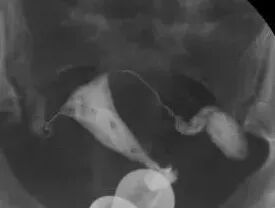

实时动态子宫输卵管碘油造影是将传统的造影改良,使患者无痛,将球囊导管置入宫颈内口,注入液体充盈球囊堵住宫颈内口后,将碘化油经导管缓慢注入宫腔,在X光透视下,动态观察碘油逐渐膨胀宫腔,流入输卵管,经伞端流入盆腔的全过程。在操作后的12~24小时,再拍一张延迟涂抹片,观察碘油在盆腔内的弥散情况。

如下图所示,这是一张正常的延迟涂抹片,碘油在盆腔内均匀弥散。